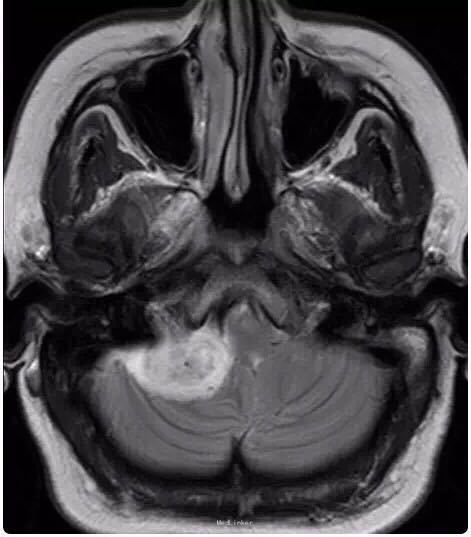

女性患者,34 岁,主因头痛、右耳听力损害以及平衡障碍 3 个月入院。

行头颅影像学检查、轴位 T1 像、轴位增强后 T1 像、冠状位增强后 T1 像以及轴位 T2 像:显示在右侧桥脑小脑角部位有一边界清楚病灶,T1 为低信号,T2 为高信号,并且伴有强化;病灶扩展至右侧颈静脉孔区,导致颈静脉孔增宽,脑干、第四脑室和小脑变形。右侧内耳道正常,病灶无颅外扩展。轴位 T2 加权 GRE 成像显示多发性病灶内出血:

诊断为颈静脉孔区神经鞘瘤。 手术切除辅助以立体定向放疗。